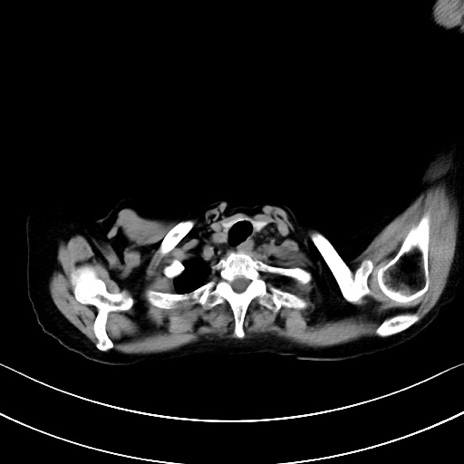

横断像

他院CT